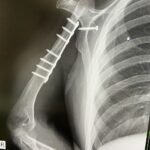

@miyabi_udenashiさん(@miyabi_udenashiさんより提供)